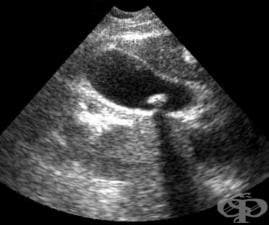

АКЦЕНТИ ОТ РУБРИКА УЛТРАЗВУКОВО ИЗСЛЕДВАНЕ (ЕХОГРАФИЯ)

АКТУАЛНО ОТ РУБРИКА УЛТРАЗВУКОВО ИЗСЛЕДВАНЕ (ЕХОГРАФИЯ)